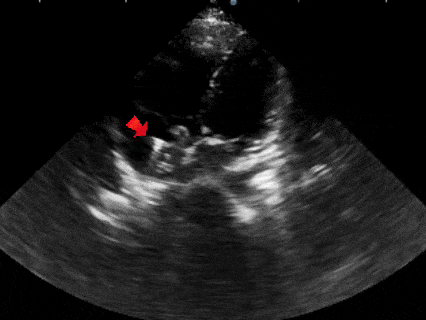

锁定后牵拉

牵拉试验时,超声下观察封堵器,封堵器结构稳定无散开,锁定成功